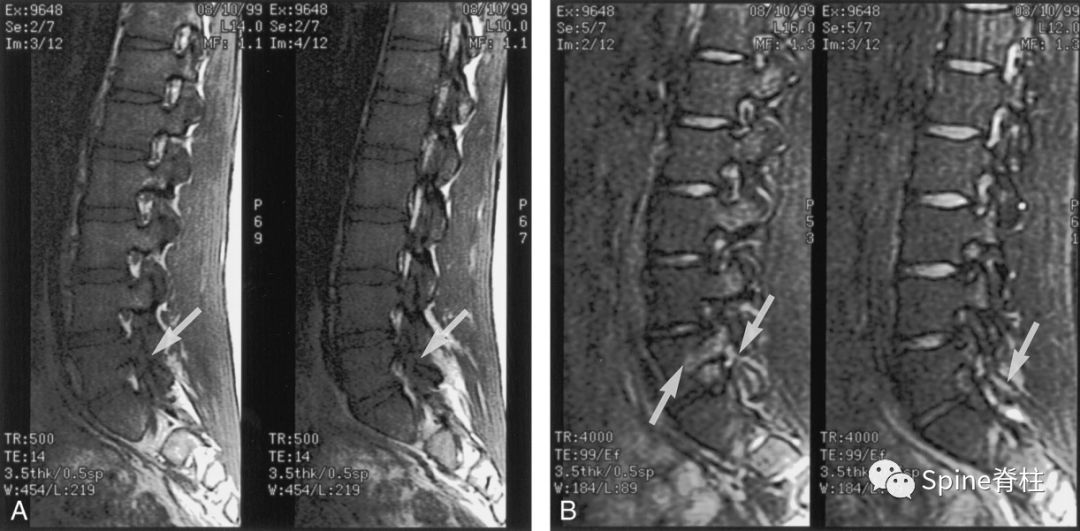

在峡部裂继发的椎体滑脱患者中MRI正中矢状面TIWI示棘突基底部与硬膜之间会出现脂肪的异常增多沉积,且椎体滑脱越严重脂肪增多也越明显。 而在尚未出现椎体滑脱的隐匿性峡部裂患者中是否也存在上述脂肪增多的影像学表现呢?最近,一项回顾性研究发现棘突基底部与硬膜之间的脂肪沉积征对隐匿性腰椎峡部裂的诊断有一定的特异性,有助于早期诊断峡部裂。

腰椎MRI正中矢状面 T1WI。A:棘突基底部和硬膜之间未见脂肪沉积;B:L5棘突基底部与硬膜之间可见线状脂肪高信号带(箭头示)

L5椎弓峡部裂典型病例一:男,32岁。A,B: 腰椎正位侧位X线片示无明显椎弓峡部裂征象; C: 腰椎 MRI正中矢状面T1WI示L5棘突基底部与硬膜之间出现脂肪高信号带(箭头示); D: 腰椎CT矢状面重建示L5椎弓峡部骨质不连(箭头示)。

L5椎弓峡部裂典型病例二:男,35岁。A,B: 腰椎正位侧位X线片均无明显椎弓峡部裂征象; C: 腰椎MRI正中矢状面T1WI示L5棘突基底部与硬膜之间出现脂肪高信号带(箭头示); D: 腰椎CT矢状面重建示L5椎弓峡部骨质不连,裂隙较细(箭头示)。